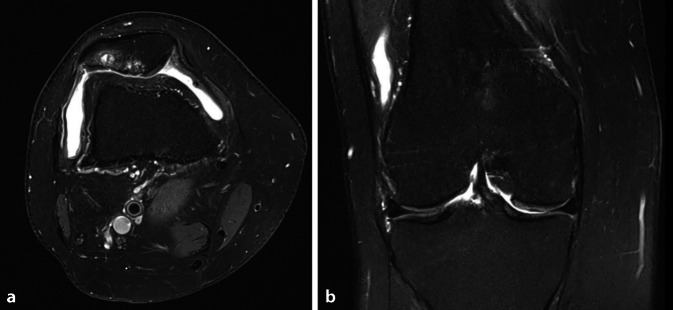

Background: Isolated patellofemoral osteoarthritis is a degenerative disease of the knee joint that may cause disabling pain and functional limitations. When conservative therapy has failed, arthroplasty can significantly improve the quality of life and mobility of affected patients. In such cases, it is important to select the most suitable implant for the patient on an individual basis. This article discusses the decision-making process between patellofemoral arthroplasty, total knee replacement, and bicondylar replacement without patellar resurfacing.

Therapeutic options: Patellofemoral arthroplasty is mainly used in younger patients and, if implanted correctly, can lead to good results and a delay in the need for total knee replacement. In older patients with isolated patellofemoral osteoarthritis, total knee replacement is usually the preferred option due to its predictable good outcomes and a lower revision rate. In selected cases, particularly with severely thinned patella, retropatellar resurfacing should not be done.